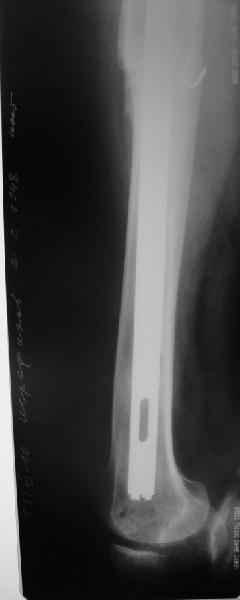

Произведено закрытое удлинение ножки эндопротеза с помощью ретроградного интрамедуллярного стержня. Продолжительность операции 3 часа. Два из них закрытое восстановление длины бедра диистрактором

таз-бедро.

А нельзя ли увидеть и профиль бедра на всем протяжении, т.е. и весь протез, и весь стержень? И фас бы с коленом.

новые снимки

Пациента удалось осмотреть недавно. Достигнутый результат сохраняется. Перелом бедра сросся. Конечность опорная и безболезненная, ходит без трости. Ножка, похоже, реинтегрировалась, как и надеялись. Снимки и фото в приложении. Комментарии приветствуются.

Надо ли что-то делать дальше, как полагаете? Убрать винты? Убрать "удлинитель ножки"? Или оставить все, как есть? Спасибо заранее.